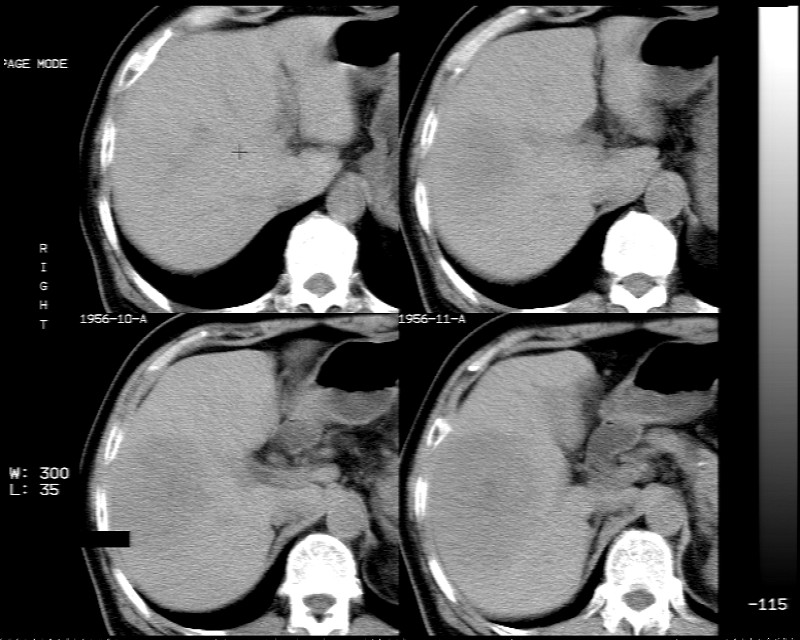

男 73岁 b超检肝右叶占位病变,afp阴性. 随访中.

肝脏右叶块状低密度影,增强后动脉期明显强化,门脉期强化减低,延迟期病灶又成低密度。考虑肝细胞癌。我认为比较典型。

平扫示:肝右后叶下段内见类圆形略低密度占位病灶,边界尚清楚,最大径约为102×71mm,ct值31~41hu。

动态增强扫描示:动脉期病灶显著不均性强化,病灶强化密度高于肝实质;平衡期病灶呈等密度;延迟扫描病灶密度略低于肝实质;三期均见占位病灶内有裂隙状无强化影。肝内胆管无扩张,腹膜后未见肿大淋巴结。

拟诊:肝右后叶下段内占位性病变,考虑为肝结节样增生。

建议进一步检查(mri/或穿刺活检),不排外肝ca。